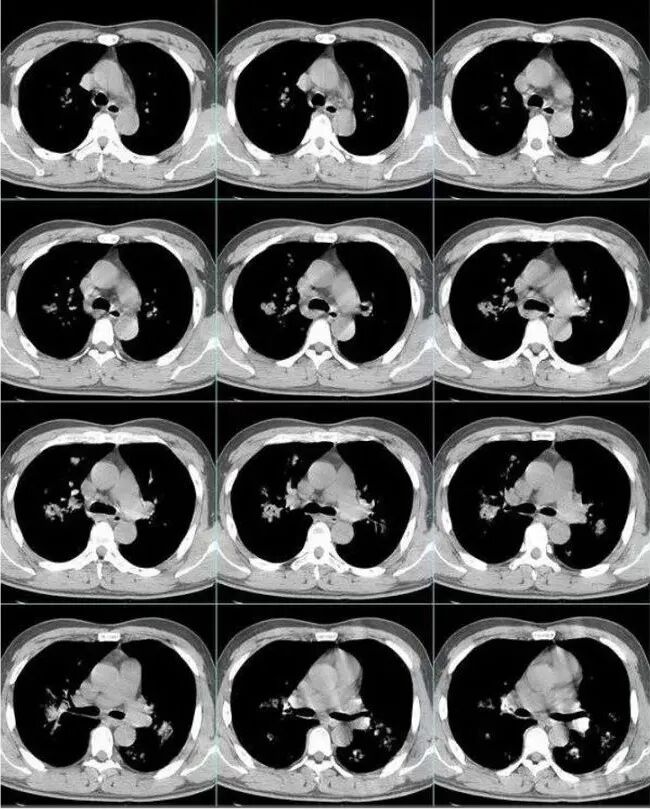

中年男性,咳嗽发热伴咳血胸痛。以左下肺大片实变混合磨玻璃为主,另两肺散在斑片状阴影,渗出明显边缘模糊,左下肺病灶部分边缘平直,病灶内未见明显空洞气囊等,未见树芽。纵隔窗显示病灶范围明显缩小提示渗出为主,双侧胸腔未见明显积液。首诊还是感染性病变,细菌,真菌,病毒,气道播散型金葡菌?非典型肺炎?

左肺实变膨胀感不强,未见枯树枝征,多发小叶改交,但不是支气管播散的腺泡结节,纵隔窗左下实变蜜度明显等于大于肌肉密度,粘液感不强,男性,病史短、有发热不支持粘液腺癌

男,52,咳嗽咳痰胸痛半月,近期加重,发热3天,声嘶伴气短1天,昨晚痰血。胸部CT:双肺多发斑片影、结节影,大小不一,密度不一,有GGO、有实性,沿支气管血管束分布,中内带多,边界不清,支气管进入,支气管充气征,似有小叶内间隔增厚,考虑:血管炎?肺水肿?鉴别感染、腺Ca、淋巴瘤等。

金黄色葡萄球菌为厌氧的革兰氏阳性球菌,可产生凝固酶和多种其他毒素及酶,其感染的病理改变中最突出的特点是化脓倾向强,尤其是MRSA肺炎具有起病急,病情进展快,病死率高的特点,早期诊断并进行足量、敏感的抗菌药物治疗对减少其发病率及死亡率具有重要作用。金葡菌肺炎常表现为多种CT征象并存,磨玻璃密度影及斑片影是最常见、最主要的CT表现,肺气囊是典型的影像表现。肺气囊是支气管周围脓肿使终末细支气管和肺泡发生坏死,当与支气管相通后坏死物质排空形成的含气空腔,表现为圆形或类圆形的薄壁空腔,壁厚1—2 mm。部分患者因起病急,使用抗生素较早,在一定程度上也影响了金葡菌感染的程度及转归,表现为磨玻璃样影及斑片影,因此在脓肿基础上形成的肺气囊亦相对较少或出现较晚。